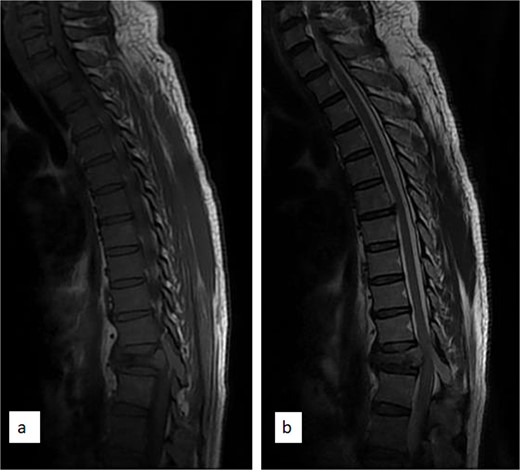

Thoracic spine MRI showed collapsed T11 vertebral body (Fig. 1), T1 isointense and T2 hyperintense extradural mass compressing the spinal cord and involving the posterior elements (Figs 1 and 2). There was no radiological evidence of metastatic lesions. He subsequently had T10–12 laminectomy, near total tumour excision, and spinal stabilization with rigid vertical strut and spinal process wire [8]. The tumour histomorphological and immunohistochemical features were consistent with NB.

Sagittal T1 (a) and T2 (b) weighted thoracic MRI images showing collapsed T11 vertebral body and tumour involvement of the T11 spinous process.